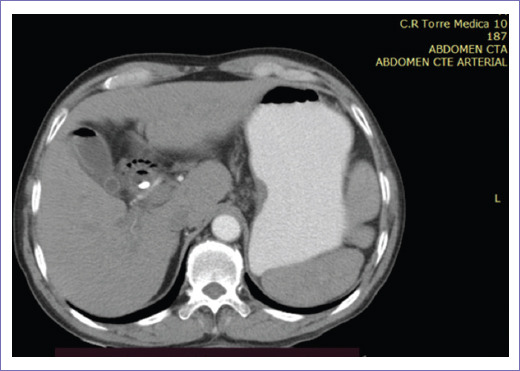

La tomografía abdominopélvica simple y contrastada de abril de 2022 reportó vía biliar intrahepática con presencia de gas en su interior de manera generalizada, colédoco con diámetro de 12 mm, prótesis que se extiende hasta conducto pancreático y segunda porción de duodeno, en la porción final se delimitaba engrosamiento focal de 15 mm, vesícula sin litos en su interior, con neumobilia (Figs. 3 y 4).